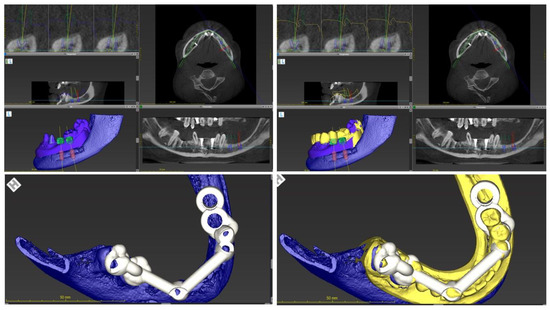

Figure 8.

Dental implant planning on lower jaw. Sagittal cuts of cone-beam computed tomography (DICOM files) are shown (a). DICOM files were superimposed to the intraoral casts (b) and to the digital wax-up (c) to determine the optimal implant position.

Figure 9.

Design of a surgical guide to be used as a reference to dental implant placement.

Due to aesthetic concerns, the surgical procedure was planned digitally. CBCT imaging of both jaws was acquired with a CBCT device (Kavo). The examination showed sufficient bone volume on edentulous spaces. Thus, no bone or soft tissue graft procedures were required. A dental impression was taken with alginate and scanned with a desktop scanner (3Shape). In addition, a wax-up was designed digitally. Dental implant planning was conducted with the software Co-DiagnostiX, as described above (Figure 8). The CBCT images were matched to the intraoral digital casts and to the digital wax-up. On the basis of the implant planning, a surgical guide was designed and printed (Figure 9).